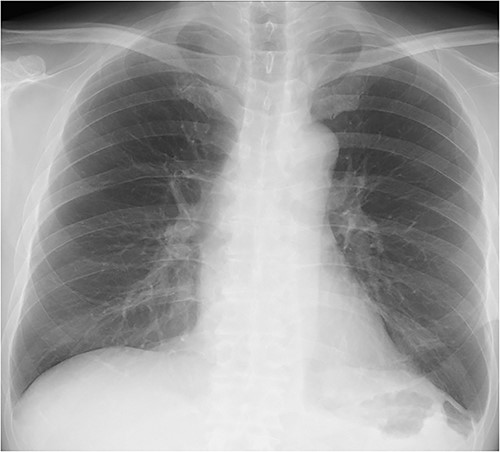

The patient was a 56-year-old man with a history of hypertension, dyslipidemia, type 2 diabetes, hyperuricemia, hypothyroidism and left renal cancer. The patient underwent open left nephrectomy and adrenalectomy for renal cancer at 48 years of age, open distal pancreatectomy for local recurrence at 54 years of age and chemotherapy for metastatic lung cancer resulting in remission. The patient presented to our hospital with a 1-week history of abdominal pain and nausea. Physical examination revealed epigastric bloating without signs of peritoneal irritation. A chest X-ray showed gastric gas shadow upon the left diaphragm. Enhanced computed tomography (CT) showed the fornix of the stomach herniating into the left pleural cavity indicating a DH. There were no signs of gastric wall ischemia, necrosis or fluid collection (Fig. 1). Laboratory results showed only a mildly elevated C-reactive protein concentration (3.17 mg/dl) but otherwise were within normal limits. The stomach was decompressed after placement of a nasogastric tube, and the patient’s symptoms were improved. However, fluoroscopy revealed that DH was not reduced resulting in a poor gastric emptying indicating failure of conservative treatment. We semi-electively performed thoracoscopic surgery.

Chest X-ray (CXR) and contrast-enhanced computed tomography (CT). (a) CXR showing gastric gas shadow projected to left hemithorax. (b) CT showing a diaphragmatic hernia in the coronal plane.